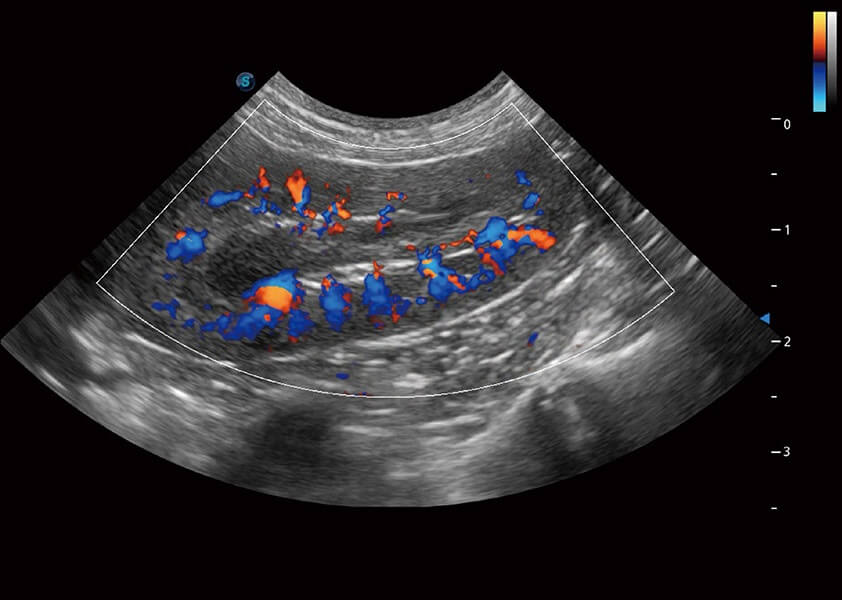

4T血流成像 微察秋毫

融合不同血流成像技术的优势,即可以提升血流成束性,同时可提高血流的视觉敏感性。

PDI 能量多普勒血流

提供高灵敏度和空间分辦率的血流图像,获得更加真实和丰富的诊断信息。

SR Flow 高分辨率血流成像

能够清晰显示细小、低速血流图像,获取传统彩色多普勒技术难以得到的细节和信息。

Micro F 显微血流成像

通过创新的Matrix E自适应滤波器和超长时间域算法,极大提升超低速微细血流的检出能力,同时更精准地滤除软组织和噪声信号,为兽用医生提供以往无法通过常规血流获得的疾病诊断信息。

Bright Flow 立体血流成像

在传统二维血流成像的基础上,呈现血流的立体感,具有动感的生命力之美。精确区分不同血管的空间关系,提高了血流的视觉敏感性。

(犬)肾脏血流